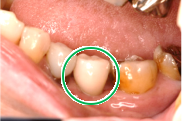

女性Kさん 70代(インプラント)

主訴

左下、ブリッジの支台になっていた奥のほうを抜歯したままになっている。ここのところを何とかしたい。

治療内容

ブリッジの奥に伸びていた部分を削り取り、インプラントを2本入れました。

所感

左下ブリッジのところを切り離し、奥を抜歯したままになっていました。このままでは、ブリッジの前方の支台になっていた歯に負担がかかり、将来抜歯になる可能性があることをお話ししました。歯がないところを補う方法には、部分入れ歯かインプラントがあることを説明すると、自分の歯と同じ感覚で食事ができるインプラントを選択されました。X-Guideを使用し埋入しました。口を大きく開けることができない方でしたので、X-Guideの長所のうちの一つを活かすことができました。

インプラント2本:¥363,000×2本=¥726,000(税込)

Before

青丸の部分を削り取りました